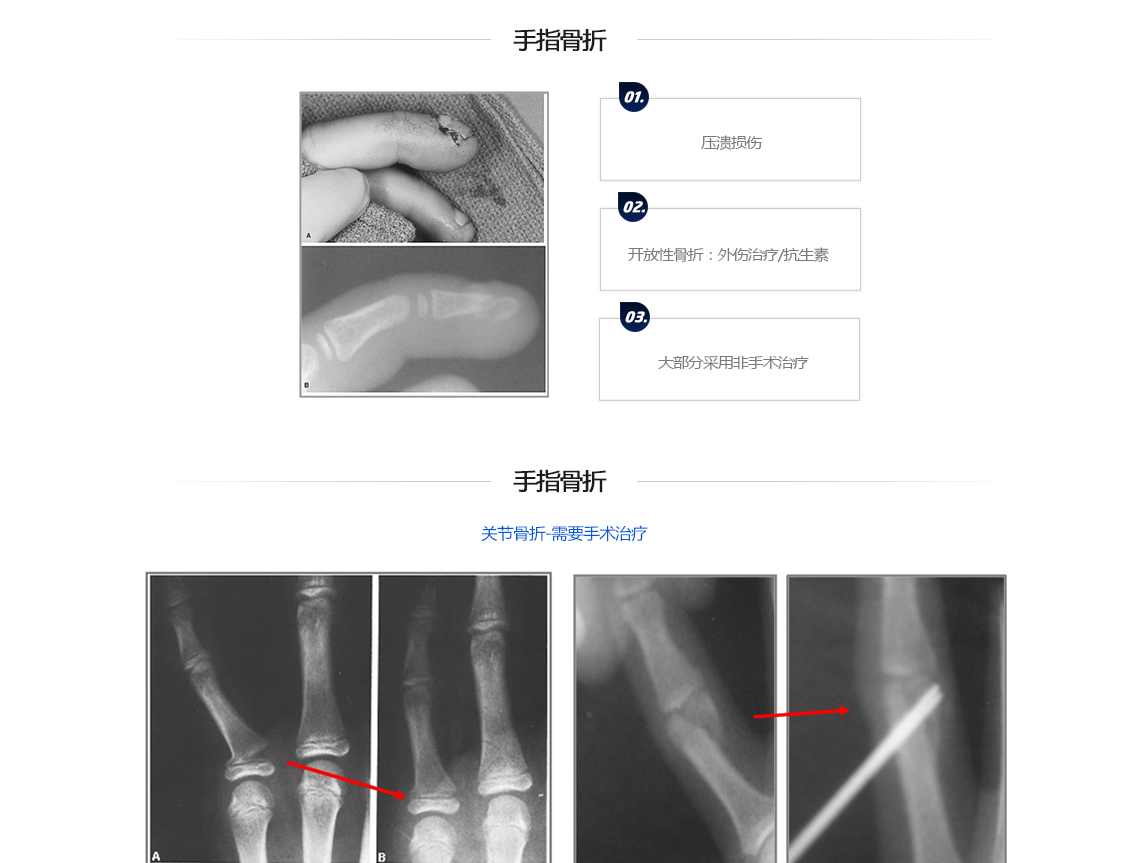

儿科骨折